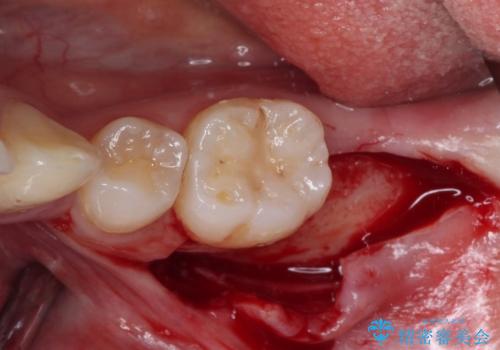

左下の欠損部は、世界中で高い信頼を得ているストローマンインプラントを用いて治療を行うこととしました。

まず生活歯髄療法を行い、その後部分矯正やインプラント処置を行いましたが、最初の処置から1年以上経っても右下奥の処置歯の神経組織に異常は認められませんでした。